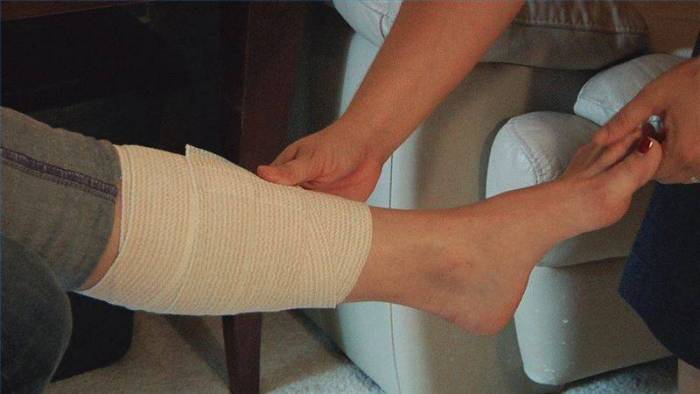

Самая распространенная проблема в процессе восстановления после снятия гипса – это борьба с отеками. Если во время ношения гипсовой повязки травмированная конечность не разрабатывалась, то опухание будет достаточно сильным (фото). Чем мазать ногу после снятия гипса, чтобы ускорить заживление? Есть медицинские средства для уменьшения отечности и народные.

- использование тугой повязки эластичным бинтом,